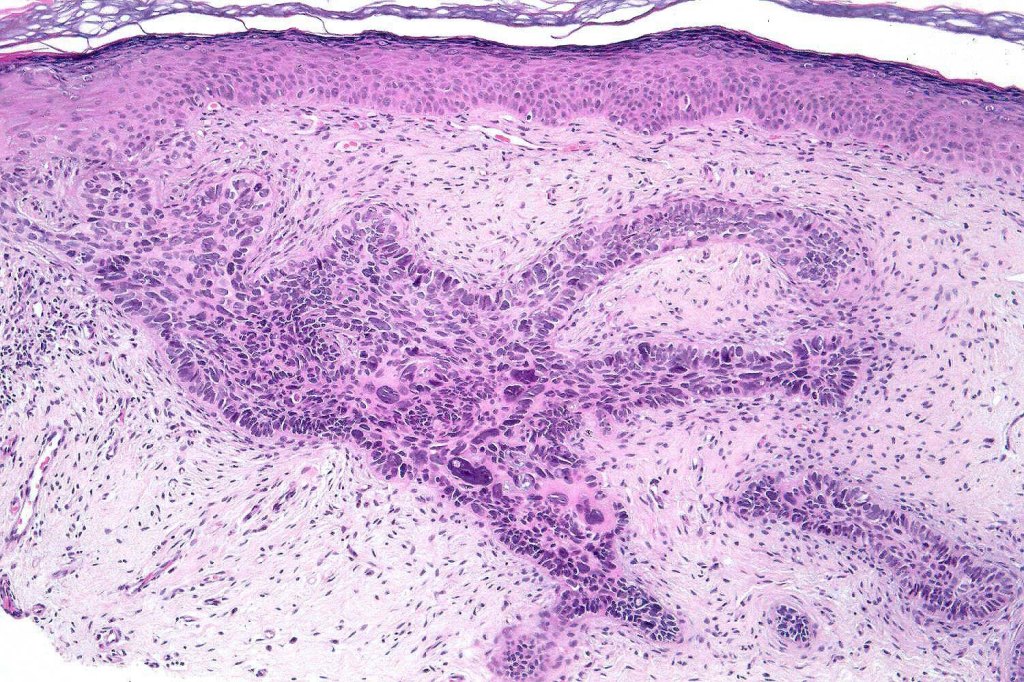

•The tumor commonly arises from the epidermis

•The epithelial component is composed of uniform small, basophilic devoid of desmosomes

•Peripheral palisading

•Retraction artifact with stromal mucin